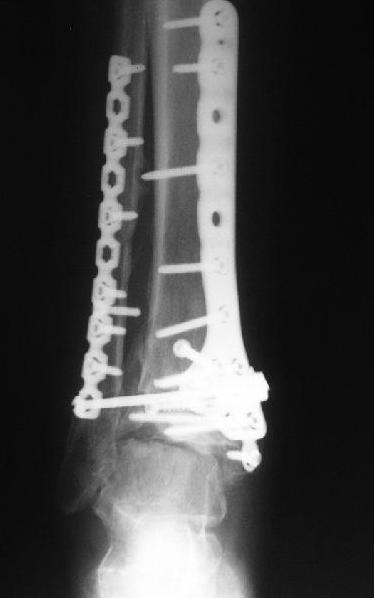

Dear коллеги,Обратилась женщина, 25 л. 8 мес. назад в одной из больниц сделан остеосинтез пилона. На сегодня ходит без дополнительной опоры, хромая на поврежденную ногу. Движения в голеностопном суставе еще есть. Снимки в приложении.

A female, 25, 8 month ago operated elsewhere. To date walks without support with pain and limp. The ankle is mobile yet. Images attached.The question is what to do now? The patient is not very keen on ankle fusion (though likely could change her mind if necessary)Is it worth to try a reconstruction procedure and what kind? Maybe it allows to restore alignment and tibio-fibular relationship - will it provide painless limb for more or less significant time?Or just remove the hardware and leave her alone until she herself comes for fusion?

CT images/xrays confirm incongruity of articular surfaces as well as intraarticular screws.

removing just those screws which have penetrated the joint may take some pain away.

Александр, добрый вечер! К сожалению, боюсь, что, кроме артродеза, ничего не осталось, упущено время. Просто убрать железо конечно можно, а куда деть вальгусную установку, "синдесмоз", признаки артрофиброза, которые прослеживаются на представленных рентгенограммах. Вопрос же стоит в качестве жизни пациентки, может ей тактично все объяснить, что чем дольше она будет так ходить, тем возможно болевой синдром будет более стойким и усилится деформация.